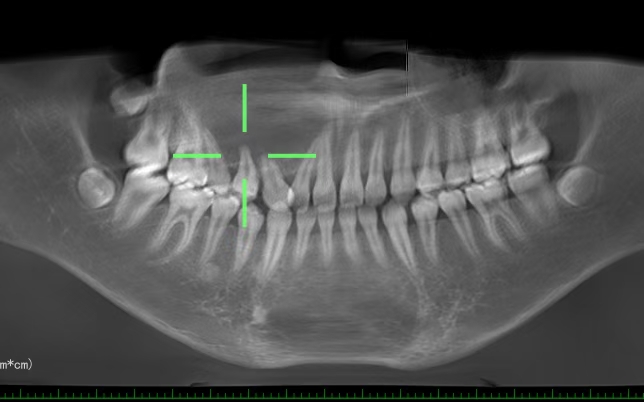

12岁孩子,巨大囊肿导致颜面变形。

现在家长的心🉑真大,12岁的小孩,外面脸和右侧鼻孔都变形了,囊肿占位面积这么大,哎~还不着急,太没意识了,看的我都着急的不行